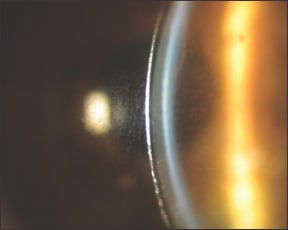

One of the most common complications of scleral lens wear is the slow buildup of debris in the fluid reservoir between the lens and the cornea during the course of a day (Figure 1). The debris can consist of mucin, mucus, epithelial cells, meibum, or makeup. Reservoir debris is more of a problem with scleral lenses that are 18mm or larger because they hold larger reservoirs and have slower fluid turnover. Mucus buildup can be considerable in patients who have severe ocular surface disease (Figure 2).

Figure 1. Buildup of debris between lens and cornea.